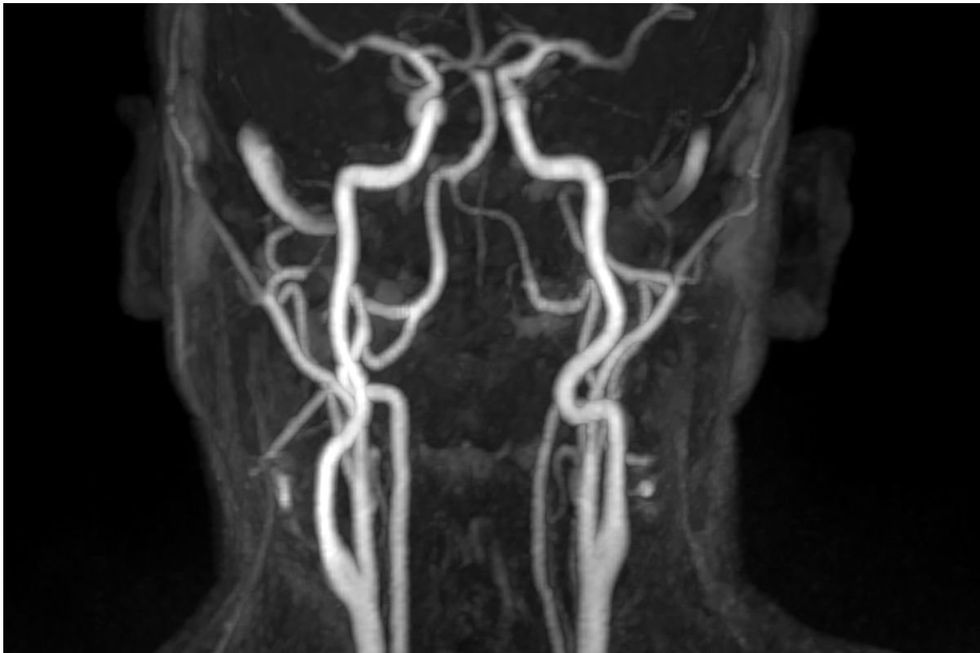

ARTERIES LEADING TO BRAIN

The downsides of taking calcium supplements extend far beyond cardiovascular problems

“Higher circulating calcium levels within the normal range are associated with increased thickness in the major arteries going to your brain and a higher prevalence of abdominal aortic calcification, and more calcified plaques in the coronary arteries,” she said.